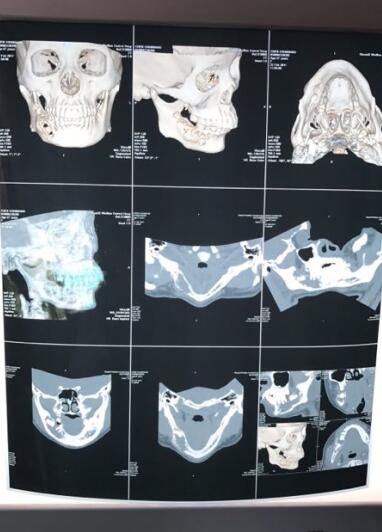

患者陈某,4个月前,偶尔发现右侧下颌有一突起包块并伴有右侧下颌磨牙松动,但因无疼痛及不适感,未就诊治疗。过了一个月后,她感觉右侧磨牙松动加重,在当地诊所就诊,拔掉了右侧松动的牙齿。今年2月来我院口腔科检查,行全口曲面断层片及颌面部三维CT显示:右下颌埋伏牙,右侧下颌骨体部骨折破坏。医生诊断为右下颌埋伏牙,右侧下颌骨恶性肿瘤。

患者CT片